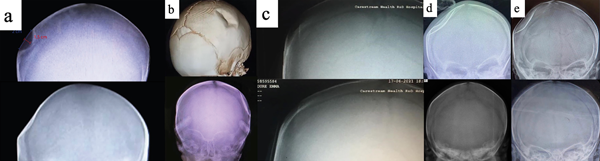

Se logró una reducción satisfactoria de la fractura deprimida en “ping pong” en todos los casos (Fig. 4). Se realizó una ecografía transfontanelar post procedimiento, la cual no evidenció lesiones agregadas. La evaluación neurológica fue normal y los pacientes presentaron buena tolerancia oral luego del procedimiento. Al día siguiente se realizó una radiografía de cráneo, la cual evidenció la reducción satisfactoria de la fractura en los 5 pacientes (Fig. 5). Los pacientes fueron dados de alta por la especialidad 24 horas luego del procedimiento con seguimiento ambulatorio.

Fig. 5: